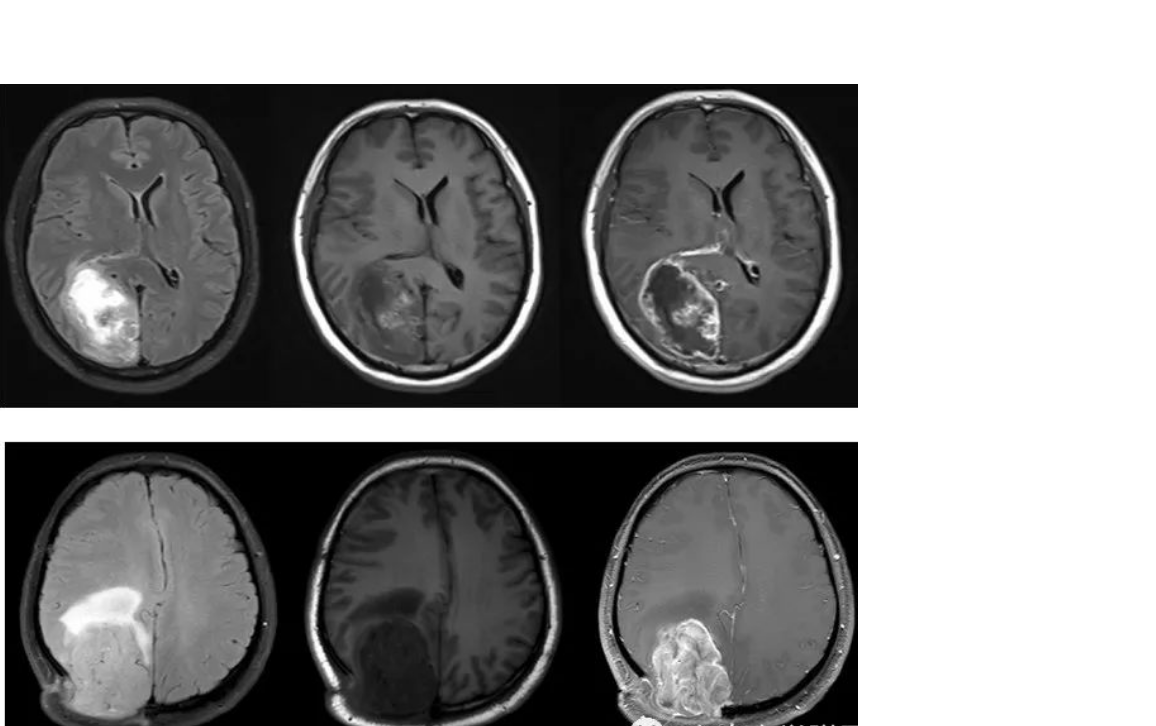

根据影像学表现和特点,晚迟发反应型可分为无病灶期、水肿期、坏死期、囊变期,各期表现可能同时或先后出现在同一患者脑部的不同部位。

2.水肿期:头颅影像学检查发现脑损伤病灶以脑白质水肿为主要特点,边界模糊。

3.坏死期:脑组织病灶局部出现坏死,可伴有出血或渗血,头颅MRI显示信号不均,增强扫描可见强化。

4.囊变期:患者头颅MRI显示放射性脑损伤病灶边界清晰并囊性变,信号接近游离水信号,有或无占位效应。囊变期病灶可较长时间稳定,但也可能急性增大,引起脑疝,患者出现意识水平下降,昏迷甚至死亡。

1.磁共振增强:放化疗后可导致血管内皮细胞损伤、坏死,造成血管内皮细胞紧密连接损害,BBB功能损害、通透性增强,在MR增强强化。MR增强上出现强化灶、新强化灶。类似肿瘤复发的影像学表现。胶质母细胞瘤放疗后,MR增强强化见于:70%:肿瘤复发、坏死(结节或多发强化区,术后3月后);30%:单侧放射性坏死(地图样强化)。